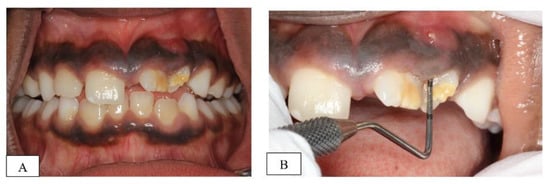

2.1. Clinical Examination and Diagnosis

2.2. Treatment Plan and Progress